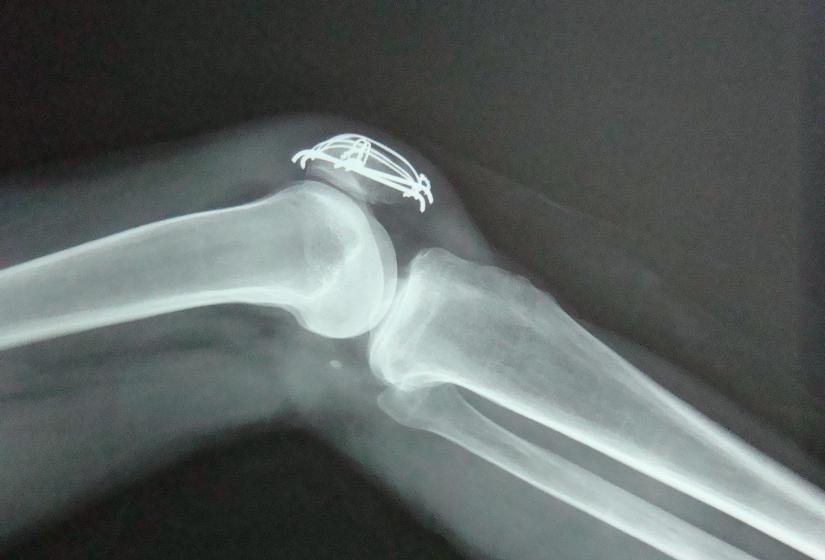

膝关节里有一个封闭的关节腔,关节腔里有少量的关节滑液。

滑液是由滑膜分泌的一种能润滑关节、减少摩擦、营养软骨的透明粘质液体。正常情况下,膝关节的滑液大概在10~20毫升。但如果关节受损、滑膜受到刺激,滑液的吸收和分泌就会受到影响,在关节腔里形成了积液。

2、积液要不要抽

对于关节积液,尽量不要随便抽,任何进入关节腔的治疗都必须在严格的无菌操作下进行,否则会造成严重的后果。